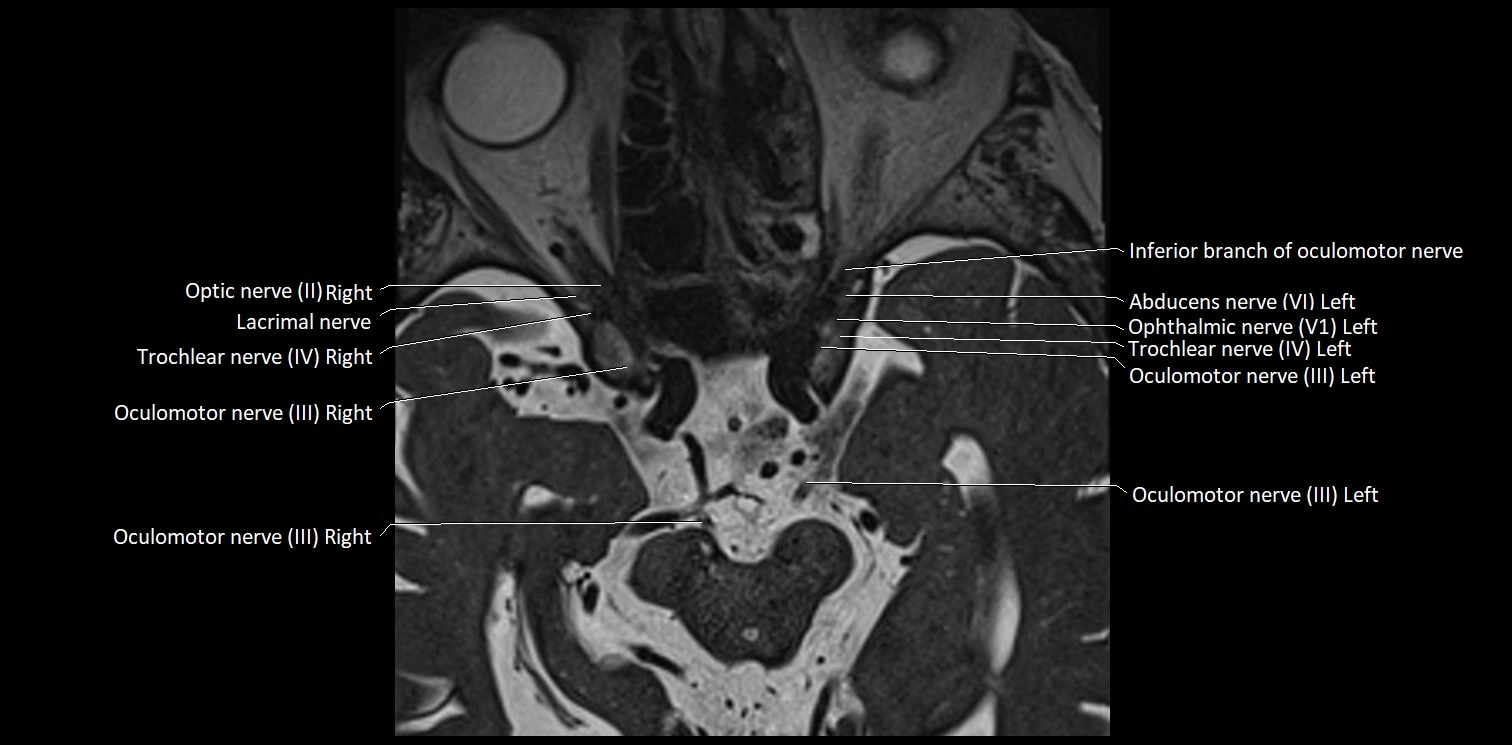

MRI Appearance

• The abducens nerve is a small, thin, linear structure

• Best visualized on high-resolution T2-weighted 3D MRI sequences (e.g., FIESTA or CISS)

• Seen as a hypointense (dark) line running from the brainstem at the pontomedullary junction, traversing the prepontine cistern, and entering Dorello’s canal under the petrosphenoidal ligament, then into the cavernous sinus, and finally the orbit

• May be challenging to visualize in standard MRI due to its small size

• Pathology may be inferred by absence, displacement, or enhancement of the nerve